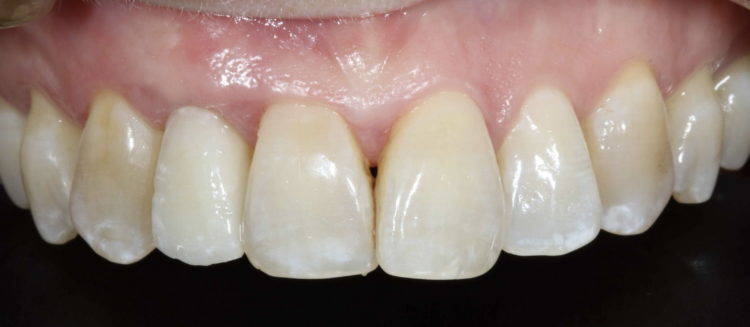

A female patient was referred for implant replacement of her failed upper right lateral incisor tooth. The tooth exhibited grade III mobility and had drifted forwards and downwards.

Clinical and CT scan assessment confirmed that the UR2 suffered from extensive bone loss with complete loss of the labial plate and was associated with a large periapical lesion which extended palatally and laterally towards the UR3. The UR3 tested positive to vitality testing.